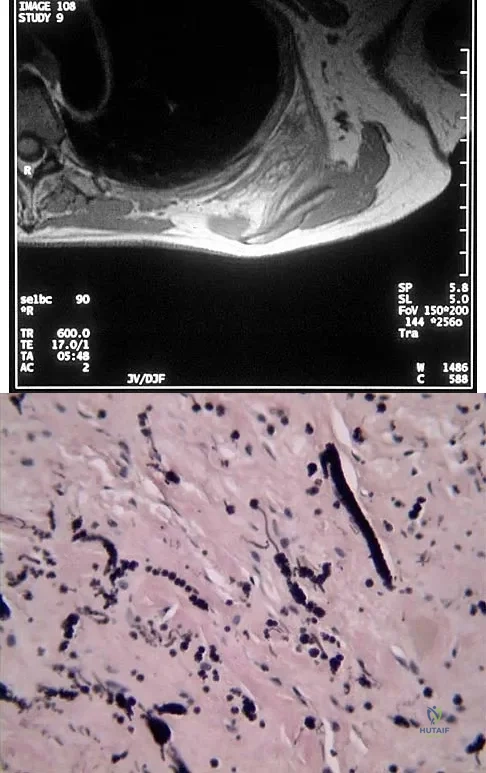

A 10-year-old boy has a painful thigh mass. A radiograph, MRI scan, and biopsy specimen are shown in Figures 42a through 42c. What is the most likely diagnosis?